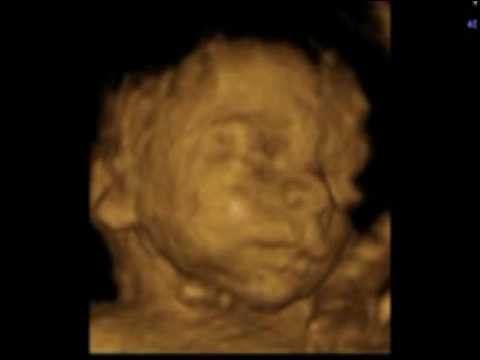

3d Ultrasound 25 Weeks Baby Videos Teilen Foto 19614624 Fanpop